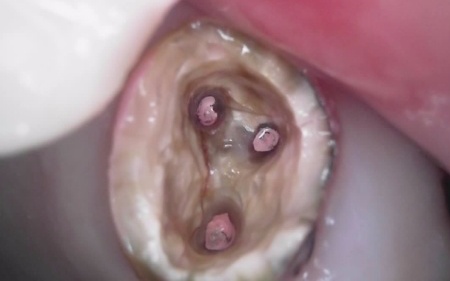

| 行ったご提案 ・治療内容 | 痛みが出ているブリッジ周辺の治療として、ブリッジの土台となっていて、歯根が割れている手前の歯(第2小臼歯)は抜き、根尖病巣を発症している奥の歯(第2大臼歯)は、根管治療を行います。 根管治療とは、感染した神経を取り除いて、歯根内部を清掃・消毒する治療方法のことです。 抜歯と根管治療を行ったあとは、欠損部を補うために、2本のインプラントを埋入する方法を提案しました。 インプラントを埋入するために必要な骨量が足りない場合は、鼻の空洞(上顎洞)の粘膜を少しずつ押し上げて骨を増やす「ソケットリフト」を併用することもお伝えしています。 インプラント治療のメリット インプラント治療のデメリット それぞれの方法について丁寧にお伝えした結果、治療に同意いただきました。 まずは、右上手前の歯(第2小臼歯)を抜きました。 抜歯後は、インプラント治療を行うために、歯を支える骨(歯槽骨)の回復を待つ必要があり、最低でも6ヶ月を要します。 約2ヶ月後、インプラントと骨が結合したことを確認して、右上奥歯2本の仮歯を作製し、手前の歯槽骨が再生するまで経過観察を継続します。 約4ヶ月後、歯槽骨の再生が確認できたため、もう1本のインプラントを埋入しました。 当院のインプラント治療は、施術の安全性と長期的な使用を可能にすることを優先して治療を行うため、通常は抜歯後に歯槽骨の治癒を待ってからインプラントの埋入を行っています。 右上奥歯2本に仮歯が入り、噛み合わせが安定した状態になったため、根尖病巣を発症している右上奥歯の治療を開始します。 また、インプラントに装着する人工歯を作製する前に、歯科医院で歯を白くするオフィスホワイトニング治療を希望されたため、治療期間がやや長くなっています。 最後に、完成した人工歯を装着し、見た目や噛み合わせに問題がないことを確認して、治療を終了しています。 |

治療中